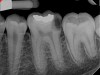

Fig 11. Preoperative radiograph. Courtesy of Dr. Guillaume Jouanny.

Figure 11

Fig 12. Postoperative radiography after full pulpotomy was performed. Courtesy of Dr. Guillaume Jouanny.

Figure 12

Fig 13. Tooth was asymptomatic at 1-year follow-up. Courtesy of Dr. Guillaume Jouanny.

Figure 13

Fig 14. Contralateral tooth at 1-year follow-up. Courtesy of Dr. Guillaume Jouanny.

Figure 14

Case 2: Pulpotomy

In this case, the tooth tested vital but showed clinical signs of irreversible pulpitis. Treatment with a full pulpotomy was chosen to improve the chances the remaining pulp would survive and remain healthy. The preoperative radiograph in Figure 11 shows extensive caries in the tooth and a slightly widened apical periodontal ligament. A full pulpotomy was performed using the BC putty (Figure 12). After the putty set, a coronal restoration was placed, and an immediate postoperative radiograph was taken and viewed. At the 1-year follow-up, the tooth was asymptomatic, and the radiograph showed continued root development (Figure 13), a healthy apical periodontium, and, importantly, no calcifications in the remaining pulp (as is often seen with a calcium hydroxide therapy). A radiograph taken of the contra-lateral tooth showed similar root development (Figure 14).